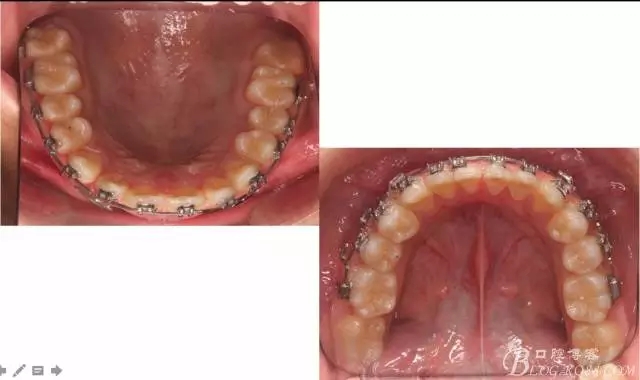

看看口內(nèi)照吧!真象“大暴牙”v假象“大暴牙”

三度深覆合,三度深覆蓋,尖牙,磨牙均二類關(guān)系!